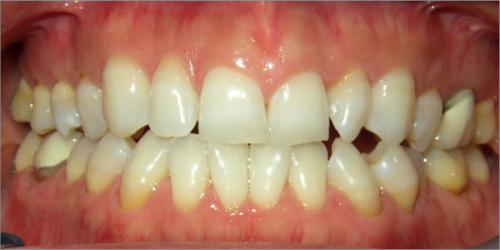

45 year old female:

Diagnosis:

- Missing upper left second bicuspid

- Lower arch crowding

- Edge to edge bite

Treatment:

- Extraction of upper & lower right second bicuspids

- Full fixed appliances

- 21 months